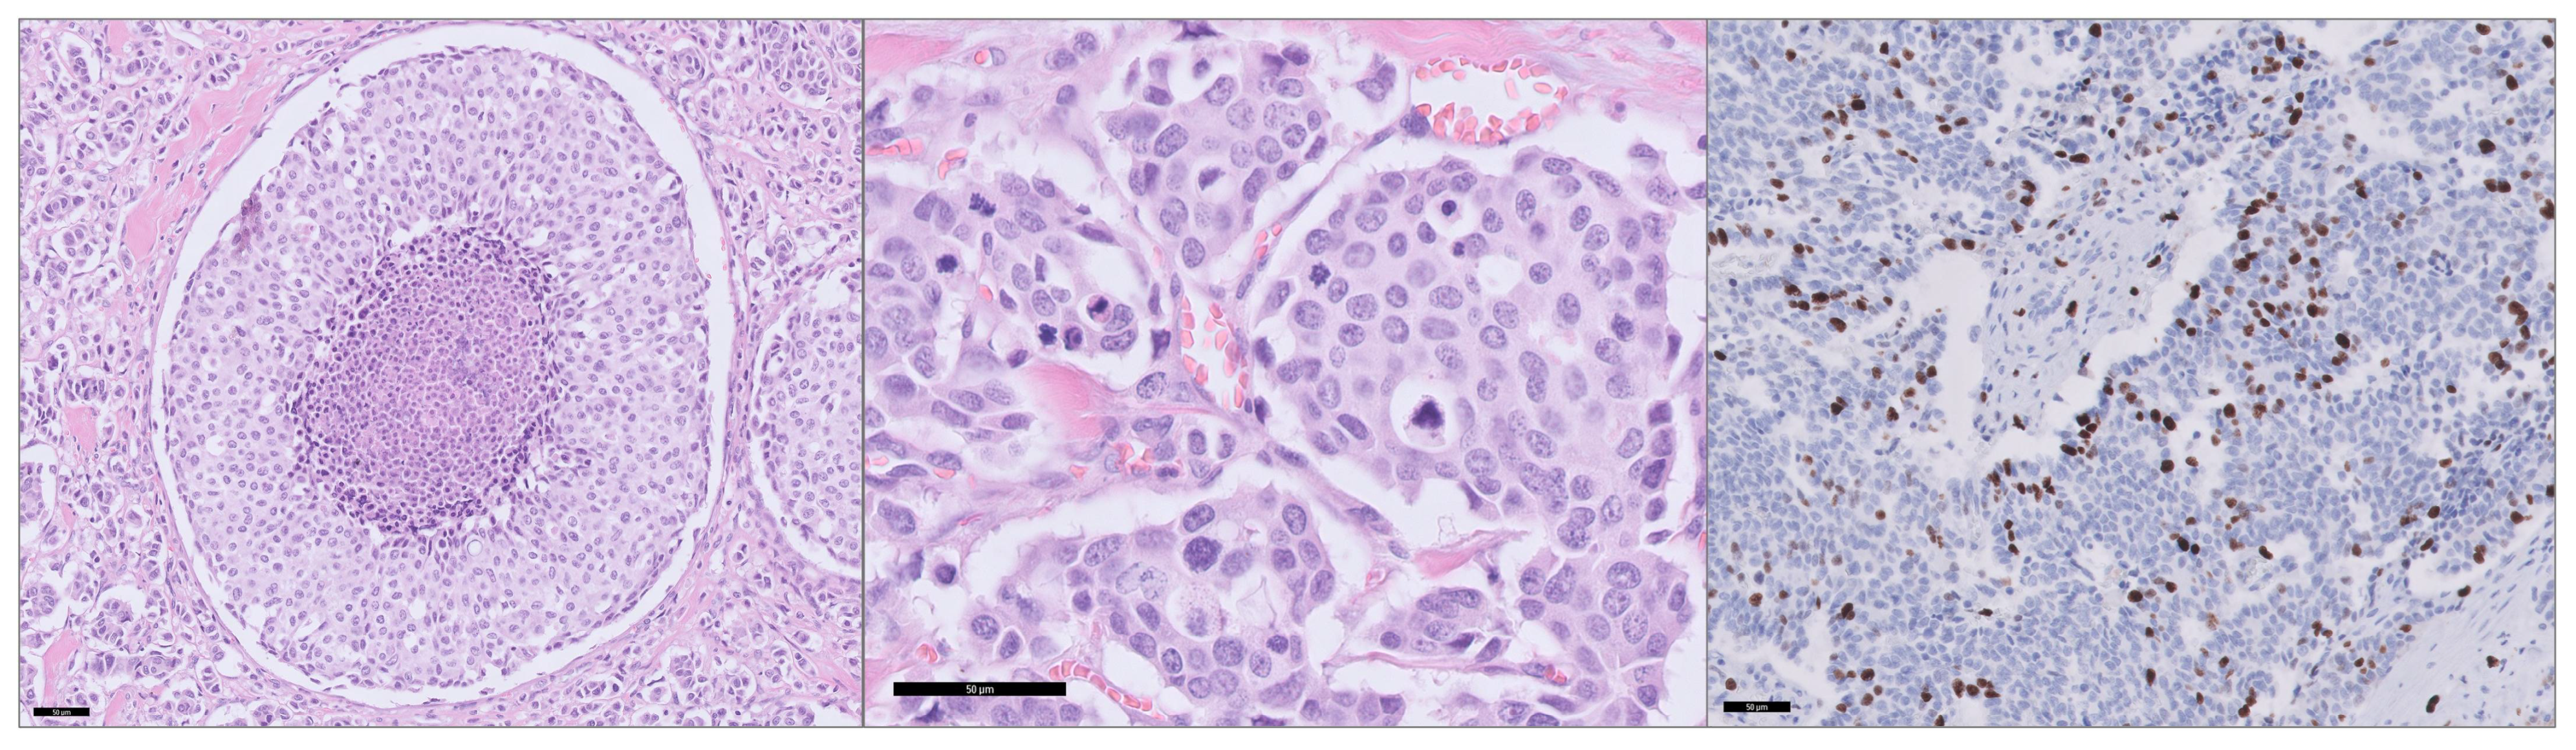

2.3. Histopathology and Construction of Tissue Microarray

2.5. Morphological Assessment

2.6. Immunohistochemistry

3.2. Morphological Features on Histopathology and IMTCGS

3.3. Biomarkers with a Potential Diagnostic and Therapeutic Consequence